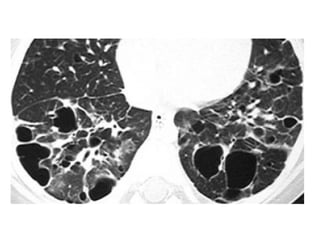

48-year-old woman with scleroderma, cough, and dyspnea and biopsy-proven

nonspecific interstitial pneumonia, high-resolution CT through lower lungs

shows scattered ground-glass opacities that are relatively symmetric in

distribution, accompanied by bronchiectasis, honeycombing is absent, note

dilated esophagus, finding associated with scleroderma